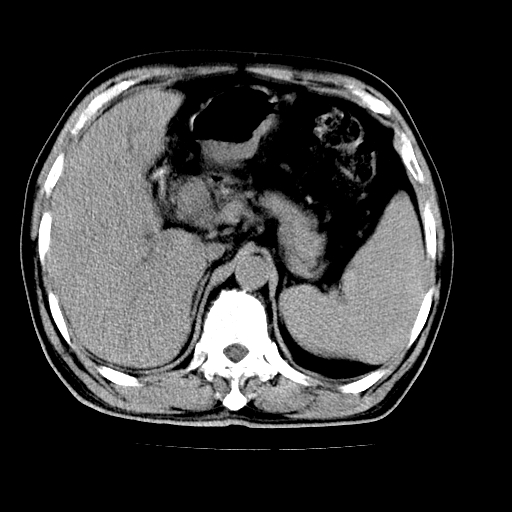

男,66岁,上腹部不适、黄染一周。彩超示:肝左叶占位,肝内胆管扩张,胆总管扩张,胆总管占位?

肝左叶不规则软组织肿块影,边缘不规整邻近肝实质受累分界不清;肝内胆管(左叶)明显扩张成“软藤状”,诊断:肝左叶胆管细胞癌。

肝左叶占位性病变,并胆管扩张,符合胆管细胞癌ct表现,门脉左支受累,左肾囊肿。窗宽太窄了,其他的看不清

左叶胆管细胞癌累及胆总管,门脉左支受侵,慢性胆囊炎胆结石,左肾小囊肿